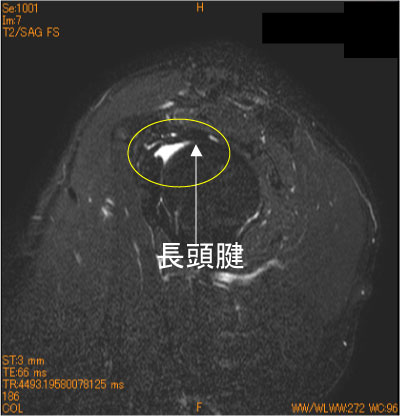

腱板疎部炎(損傷)-肩関節MRI-

30代男性。重い物を持って以来の疼痛肩。夜間痛(+)。

疼痛肩で、腱板断裂を認めない場合は、必ず、腱板疎部を注意深く、観察する。

病変は関節腔側にあるので、通常の治療に反応しない。

![]() Obl. Sag T2WI 脂肪抑制 |